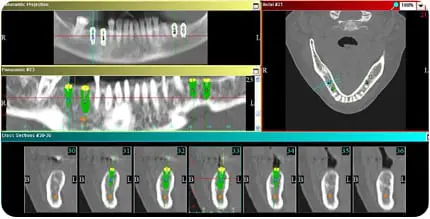

What technology is used in planning & placement of dental implants?

As part of a comprehensive evaluation in planning dental implants, advanced dental imaging and digital technologies are utilized to ensure accurate evaluation of jaw bone quality and identification of optimal implant placement sites.

These technologies include:

- 3D CBCT imaging

- digital scans

- digital or virtual implant planning

- 3D printing

- custom surgical guides

In combination, the use of these advanced technologies by an experienced surgical and restorative implant clinician help ensure precise dental implant placement, for predictable and successful treatment results.

What is 3D CBCT imaging, and why it's needed for dental implants?

A 3-dimensional cone beam computed tomography– or 3D CBCT– imaging is the only way to see the cross-sectional and three-dimensional view of your jawbone and any existing teeth.

While a typical digital x-ray may provide some initial clues about your bone, only a 3D CBCT provides for essential measurements of:

- bone height & width

- bone density

- whether bone grafting may be needed

- proximity to anatomical structures (such as nerve & sinus areas)

- whether immediate implant placement is appropriate

It’s only with the 3D CBCT imaging that a full and accurate assessment can be made by an experienced implant clinician, in preparation for the surgical placement of dental implants.

Evaluation of a 3D CBCT scan by an experienced implant clinician help determine whether implant placement is possible, or if another treatment approach may be recommended.

A three-dimensional cone beam computed tomography (3D CBCT) is necessary to evaluate the bone quality, need for bone grafting, and optimal placement and type of dental implants.

Get complete 3D CBCT diagnostics for digital planning

Your dental implants treatment is unique, and customized just for you. Dr. Simos will consider your goals and review with you all aspects of your 3D CBCT imaging and digital scans in order to give you a clear plan that works for you.